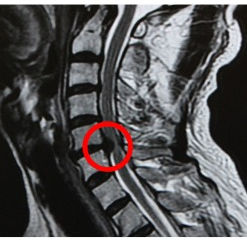

交通事故のむち打ちで手がしびれる症例

今回は交通事故でむち打ちになり、手や肩、腕にシビレや知覚鈍麻が出ている症状についてお話しします。 むち打ちにも様々な症状がありますが、シビレなどの神経症状が出ているような時はまず『頚椎ヘルニア』を疑います。非常に強い衝撃が頭部に加わった際は、緊急性を要する脳内出血などで神経...